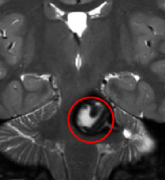

影像對(duì)比

INC巴教授緊急搶救為她全切病灶

不過(guò)幸運(yùn)的是,彼時(shí)正好是巴教授中國(guó)行示教手術(shù)期間,貝貝的父母得知后便立即向巴教授進(jìn)行咨詢,巴教授的建議是“在目前的情況下,她需要盡早手術(shù),因?yàn)檫@不是藥物可以治療的。目前血腫已經(jīng)很大了,更加危機(jī)的情況可能是再次出血。

貝貝父母當(dāng)即決定讓巴教授為貝貝進(jìn)行手術(shù),由于情況緊急,巴教授調(diào)整手術(shù)排期,經(jīng)過(guò)緊急搶救,不但全切病灶,保住了貝貝的生命,而且在術(shù)后意識(shí)恢復(fù)清醒,四肢活動(dòng)自如。